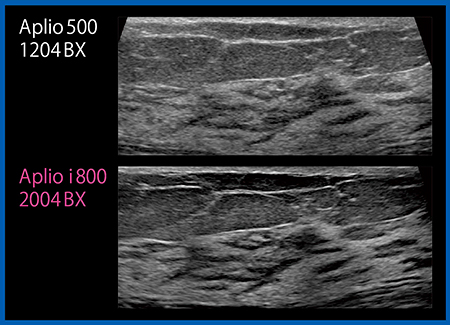

もう一つのリニアプローブ「PLI-2004BX」(8〜24MHz)は,業界最高レベルの高周波を出力でき,かつ従来プローブと同等に深部の観察も可能である。非常に高い分解能が得られ,コメド型DCISでは上皮増生や間質構造,点状高エコーといった内部構造まで観察することができる(図2)。

図2 リニアプローブPLI-2004BX(下)と従来プローブ(上)の画像比較